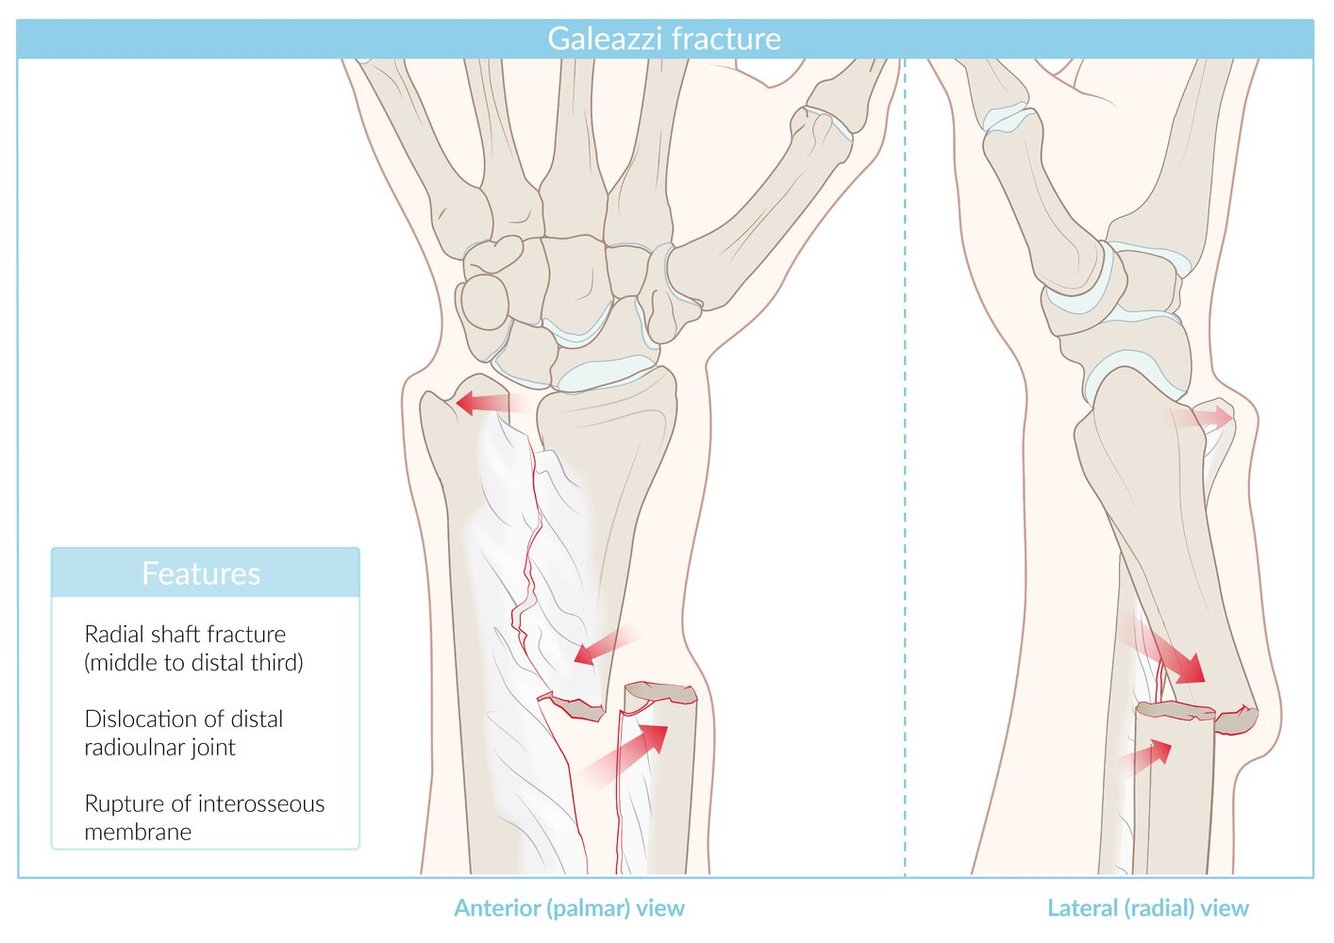

Galeazzi forearm fracture